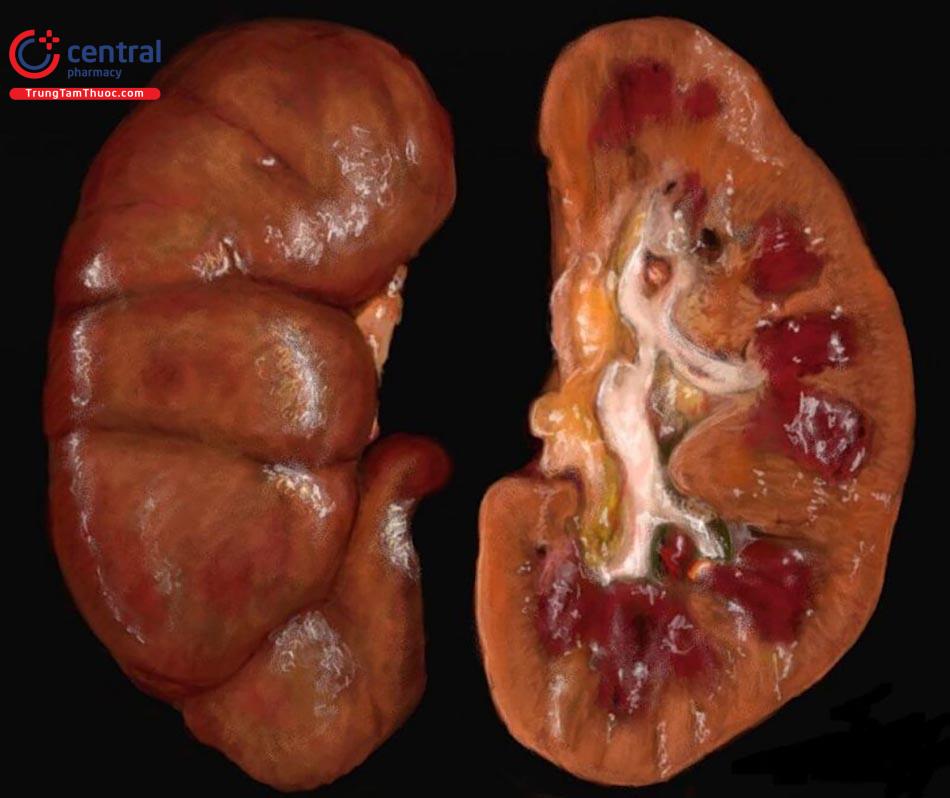

Tổn thương mô

Có 2 loại tổn thương:

- Tổn thương tiên phát: do các tác nhân gây viêm gây nên tổn thương tại chỗ rồi ổ viêm hình thành. Tổn thương có thể rất nhỏ như kim châm, trầy xước hoặc rất trầm trọng, có thể gây ra hoại tử tế bào như dập nát do chấn thương, nhiễm khuẩn độc lực cao,...

- Tổn thương thứ phát: nguyên nhân xuất phát từ các rối loạn tại ổ viêm. Phản ứng của cơ thể cũng là 1 nguyên nhân khác gây ra ứ máu và tạo ra nhiều chất làm thiểu dưỡng, gây tổn thương hay thậm chí khiến tế bào bị hoại tử.